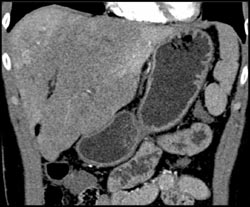

Hepatic Congestion With Patchy Enhancement